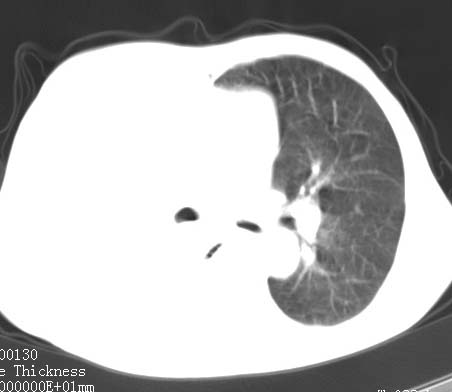

病人女 60岁 咳嗽 气促十余天,大叶性肺炎.

右肺上下叶均见 大片状密度增高影,边界清晰,其内可见支气管充气征,气管支气管通畅。纵膈略向右移位,其内无肿大淋巴结影。首先考虑炎性病变。不排除一些特异性的炎症。不知道发烧吗??wbc高吗??建议治疗后复查!!